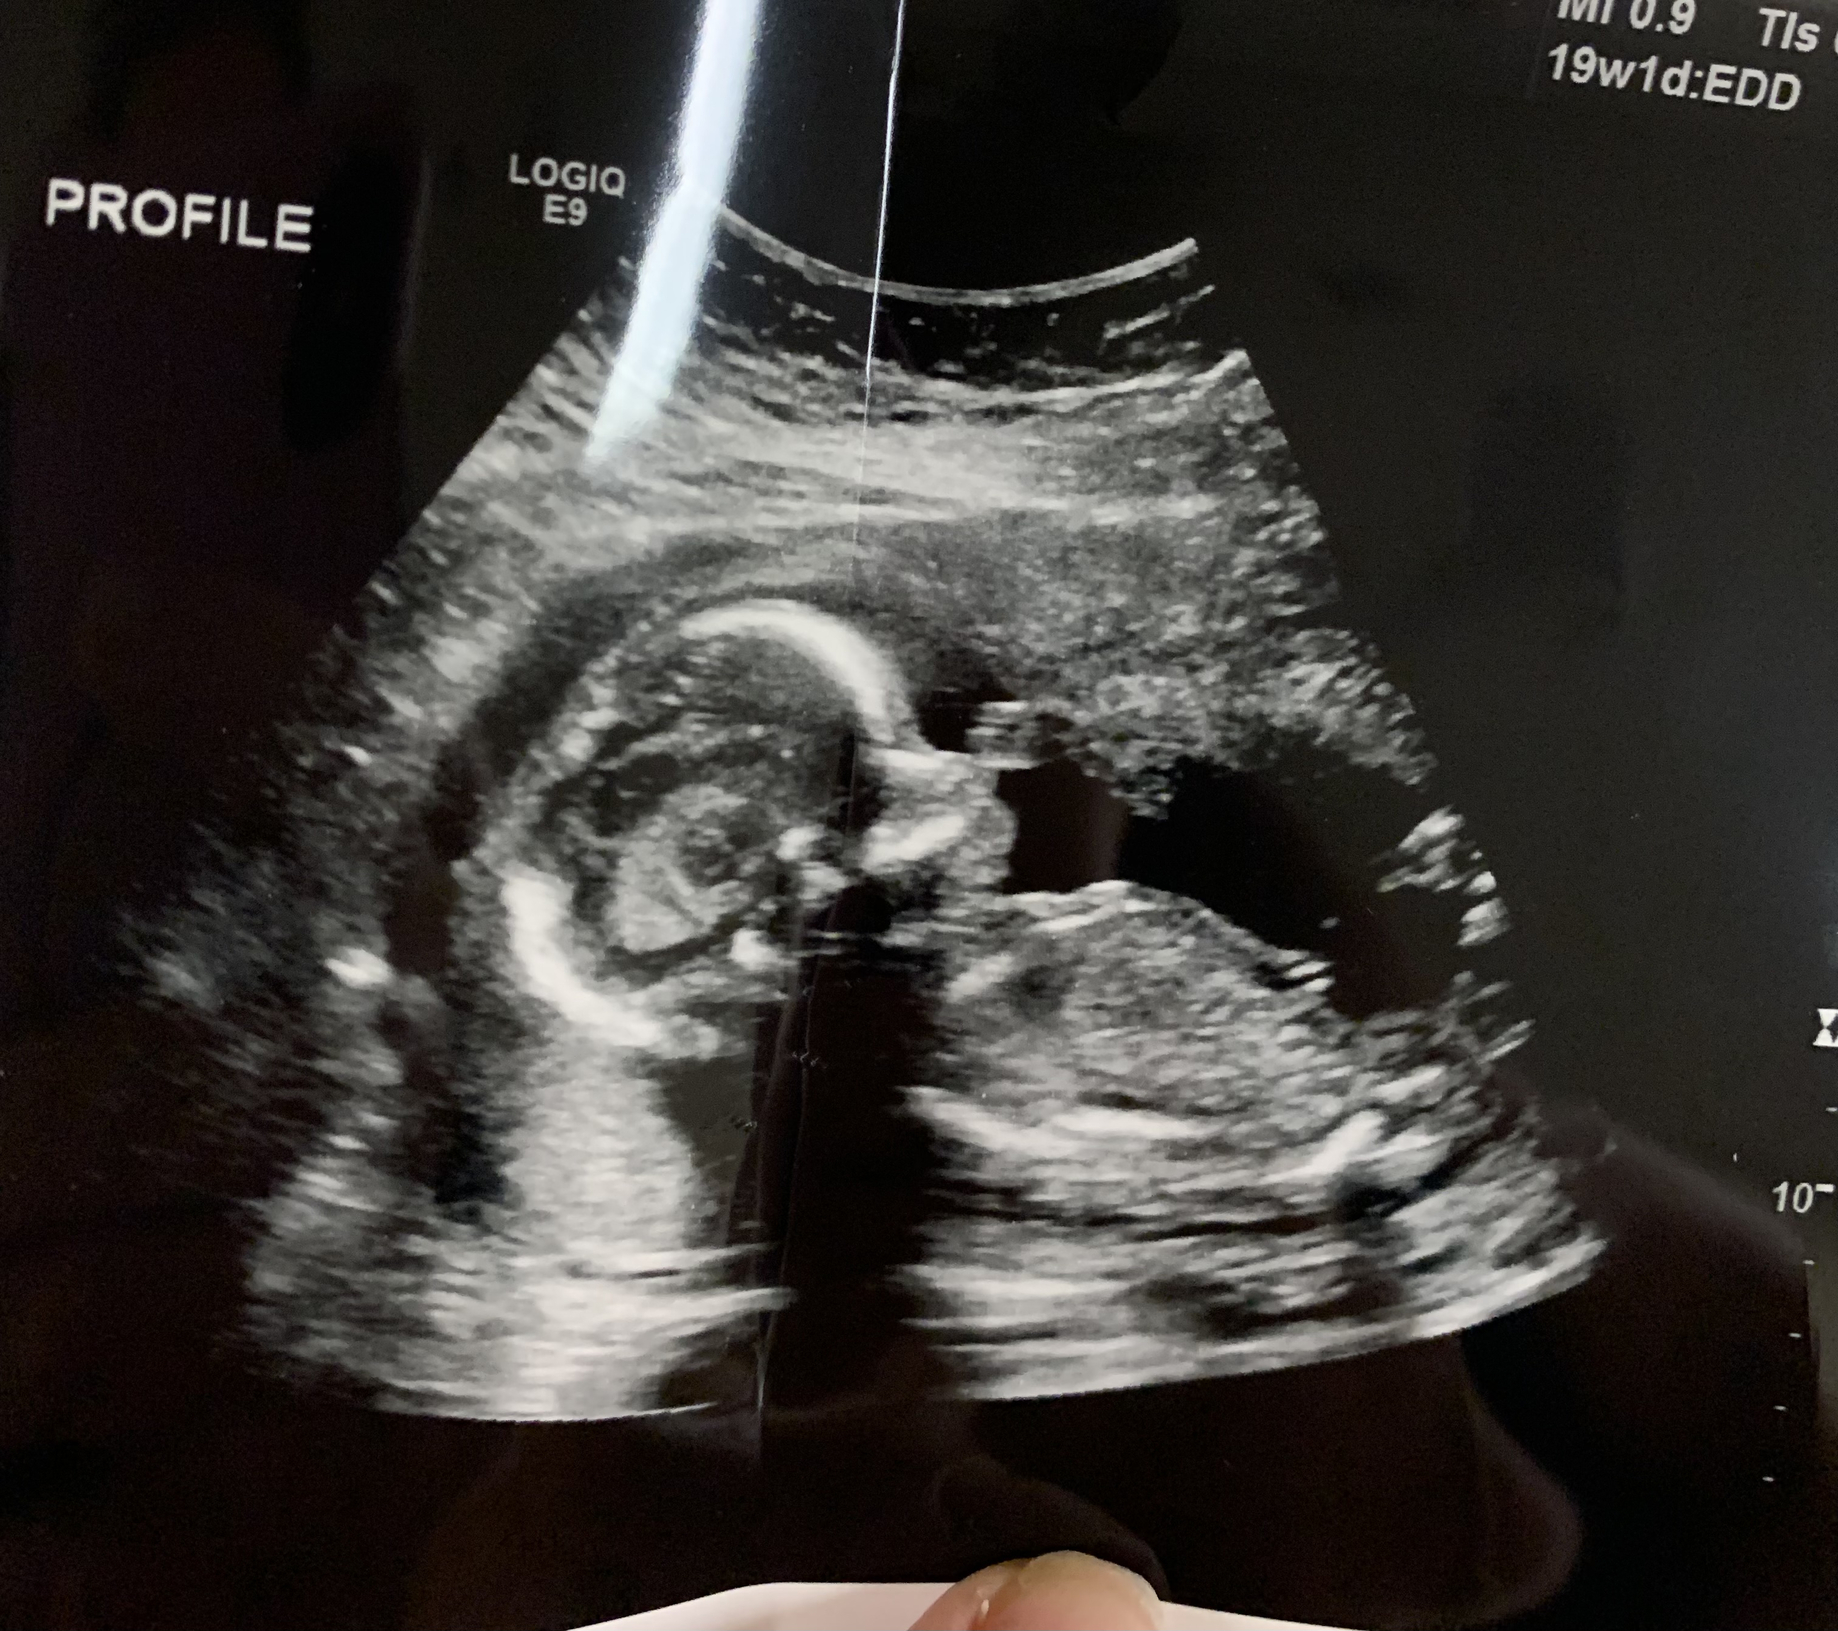

Here is a little boy at 19 weeks! We also got another pic that VERY clearly shows he is a boy which my husband is proudly sending everyone🤣 All measurements were normal but they did bring in doctor who told me it looks like I have a velamentous cord insertion (VCI) for my umbilical cord. She told me it wasn’t a big deal but my OB will tell me more. A quick Google search says it may just be something to monitor more closer to delivery. I’m not too worried- just glad babes is in there and doing well!

All measurements were normal but they did bring in doctor who told me it looks like I have a velamentous cord insertion (VCI) for my umbilical cord. She told me it wasn’t a big deal but my OB will tell me more. A quick Google search says it may just be something to monitor more closer to delivery. I’m not too worried- just glad babes is in there and doing well!